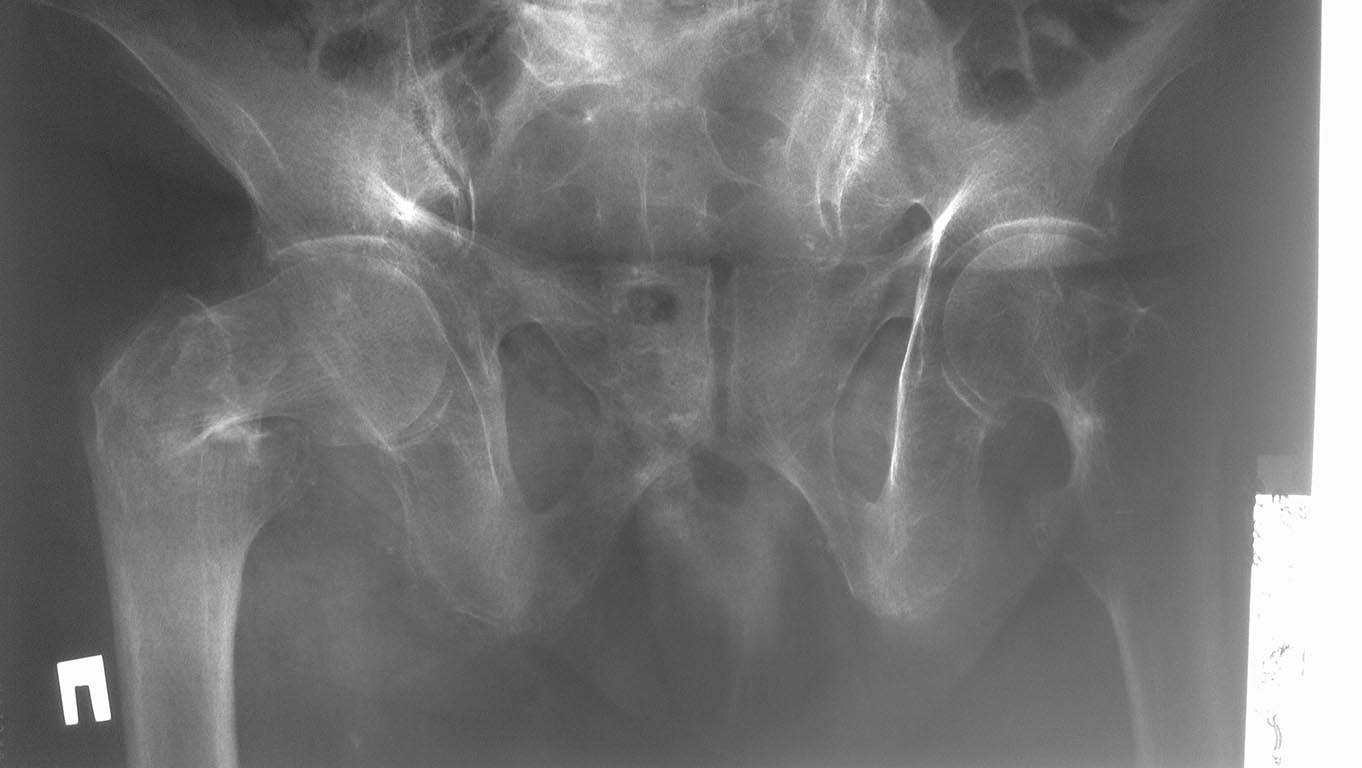

Чрезвертельный или базальная шейка?

Пациентка 1922 г.р., не тучная, без отягощенной соматической патологии, бытовая травмаГоспитализирована. Не определена тактика лечения ввиду сложности оценки типа перелома и, соответственно, тактики леченияЕсли это чрезвертельный перелом, то вариантов выбора может стать PFN или угловая пластинаЕсли это базальный (латеральный перелом) шейки - то, очевидно, стоит рекомендовать эндопротезирование сустава (масса до 100 кг)Помогите оценить ситуациюСпасибо за все ответы

думаю возможны оба варианта лечения- эндопротез даст возможность более ранней нагрузки. Еще один плюс за ЭП- выраженный остеопороз судя по снимкам. Если все же ставить гамму, то предусмотреть возможность интраоперационной аугментации шейки костным цементом.

Чтобы было меньше сложностей с оценкой типа перелома, надо не лениться вывести конечность из наружной ротации при рентгенографии. Если условия позволяют, можно и сделать и КТ.

Перелом тут вполне для остеосинтеза, эндопротез избыточен. Насчет аугментации - если доступна, не помешает. В любом случае - надо хорошо потянуть (традиционно - тракционный стол, или можно дистрактор "крыло таза - дистальное бедро", если видели). Точка входа - медиальнее верхушки вертела. Шеечный винт - максимальной длины, до хряща буквально, и не выше центра шейки. Диастаз устранить сразу до контакта компрессией по оси шеечного винта.

А мне кажется, что это не базальная шейка и даже не чрезвертельный, а межвертельный перелом бедра с отрывом латерального края большого вертела. Что то похожее - на картинке.

Классический базальный перелом шейки.